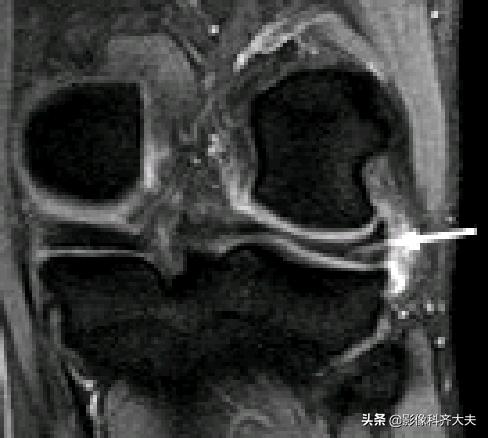

膝横韧带:

腘肌腱腱鞘:

后股板韧带:

关节内气体伪影:

内侧半月板后角上隐窝: